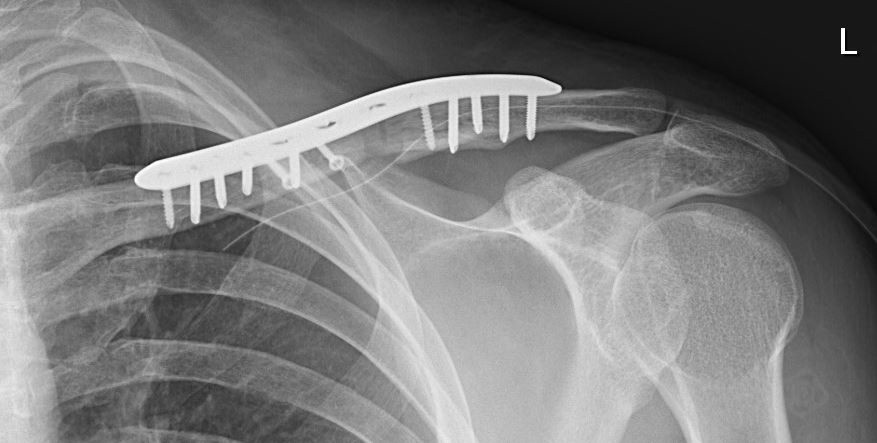

Assessment 6 months after surgery demonstrated a full active range of motion of the left shoulder and flow permeability of the left subclavian artery on duplex ultrasound (Fig. 4).

Figure 4: Radiographs 6 months after trauma demonstrate complete bony healing of the clavicle fracture.